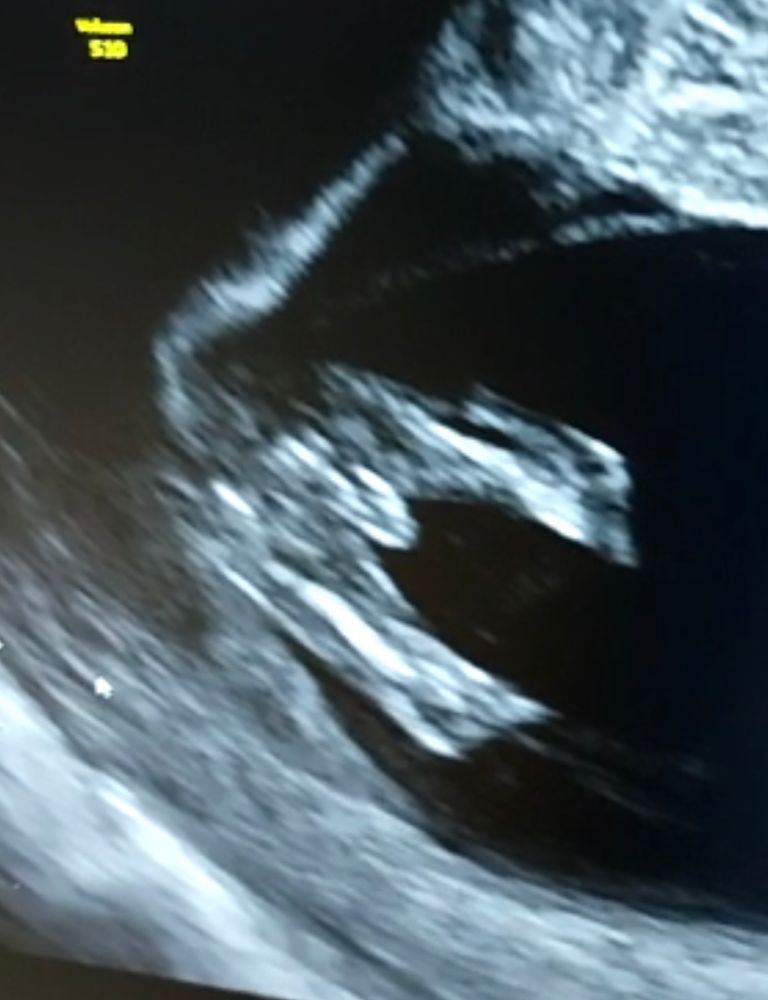

Девочка))

вот смотрите на мальчика. Нам тут 12 недель всего а пипка уже не даёт сомнения)